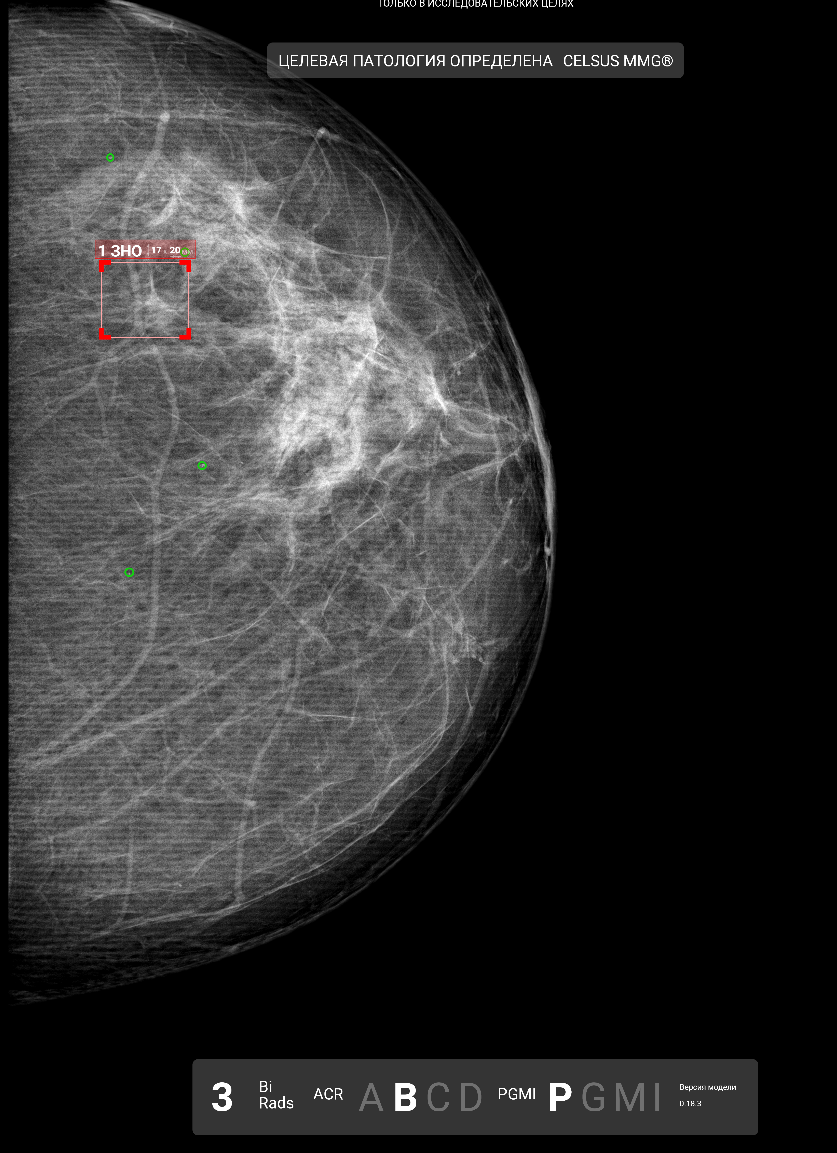

Пример протокола по ММГ

В статье предполагается, что текстовые отчёты будут генерироваться с помощью LLM на основе предиктов картиночных нейронок. С этим мне пока согласиться сложно. Я не очень понимаю, какие преимущества LLM дают по сравнению с детерминированным алгоритмом генерации, а вот потенциальные проблемы лежат на поверхности (галлюцинации и всё такое). В теории можно предположить вариант с суммаризацией текстового отчёта, истории болезни и направления терапевта на исследование, но и тут я пока не готов сделать ставку исключительно на LLM.